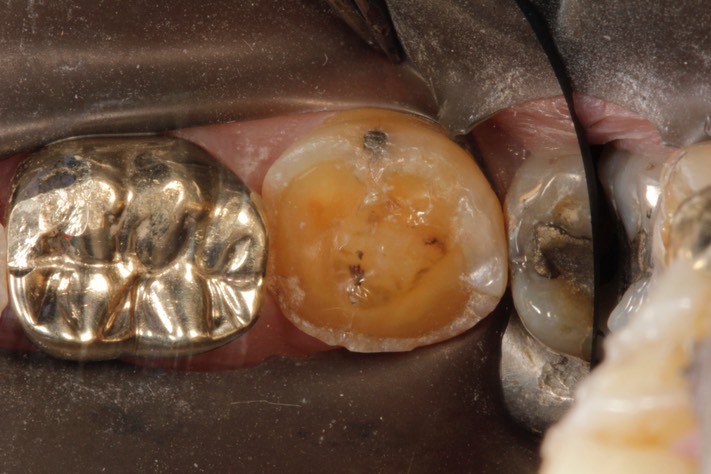

Larry Fujioka #18 pre-op